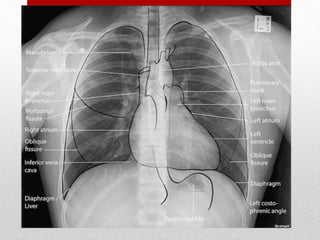

CHEST

• Blunt trauma to the chest may involve the:

• chest wall, thoracic spine, heart, lungs, thoracic aorta

and great vessels, and rarely the esophagus.

• Occult Thoracic Vascular Injury

• Penetrating Thoracic Trauma

Hemothorax and

Pneumothorax - most

common injuries from both

blunt and penetrating

thoracic trauma